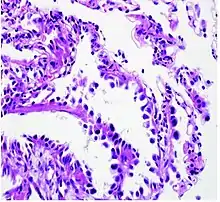

Histopathology

If possible, a biopsy of any suspected lung tumor is performed in order to make a microscopic evaluation of the cells involved and is ultimately required to confirm diagnosis.[7] Biopsy should be attempted in distant lesions first to establish a histologic diagnosis and to simultaneously confirm metastatic staging. The biopsy material is also used to analyze whether the tumor express any specific mutations suitable for tageted therapy (e.g. EGFR mutation or ALK mutation). Biopsy can be accomplished via bronchoscopy, transthoracic needle biopsy, and video-assisted thorascopic surgery (VATS).[4]

While sputum cytology has been shown to have limited utility, thoracentesis, or aspiration of pleural fluid with an ultrasound-guided needle, should be performed when pleural effusion is present. When malignant cells are identified in the pleural aspirate of patients highly suspect for lung cancer, a definitive diagnosis and staging (stage IV adenocarcinoma of the lung) is established.[4]

Adenocarcinoma of the lung tends to stain mucin positive as it is derived from the mucus-producing glands of the lungs. Similar to other adenocarcinoma, if this tumor is well differentiated (low grade) it will resemble the normal glandular structure. Poorly differentiated adenocarcinoma will not resemble the normal glands (high grade) and will be detected by seeing that they stain positive for mucin (which the glands produce). Adenocarcinoma can also be distinguished by staining for TTF-1, a cell marker for adenocarcinoma.[29]

As discussed previously, the category of adenocarcinoma includes are range of subtypes, and any one tumor tends to be heterogeneous in composition. Several major subtypes are currently recognized by the World Health Organization (WHO)[1] and the International Association for the Study of Lung Cancer (IASLC) / American Thoracic Society (ATS) / European Respiratory Society (ERS):[30][31][32] lepidic predominant adenocarcinoma, acinar predominant adenocarcinoma, papillary predominant adenocarcinoma, micropapillary predominant adenocarcinoma, solid predominant adenocarcinoma, and solid predominant with mucin production. In as many as 80% of these tumors, components of more than one subtype will be recognized. Surgically resected tumors should be classified by comprehensive histological subtyping, describing patterns of involvement in increments of 5%. The predominant histologic subtype is then used to classify the tumor overall.[2] The predominant subtype is prognostic for survival after complete resection.[33]

To reveal the adenocarcinomatous lineage of the solid variant, demonstration of intracellular mucin production may be performed. Foci of squamous metaplasia and dysplasia may be present in the epithelium proximal to adenocarcinomas, but these are not the precursor lesions for this tumor. Rather, the precursor of peripheral adenocarcinomas has been termed atypical adenomatous hyperplasia (AAH).[10] Microscopically, AAH is a well-demarcated focus of epithelial proliferation, containing cuboidal to low-columnar cells resembling club cells or type II pneumocytes.[10] These demonstrate various degrees of cytologic atypia, including hyperchromasia, pleomorphism, prominent nucleoli.[10] However, the atypia is not to the extent as seen in frank adenocarcinomas.[10] Lesions of AAH are monoclonal, and they share many of the molecular aberrations (like KRAS mutations) that are associated with adenocarcinomas.[10]